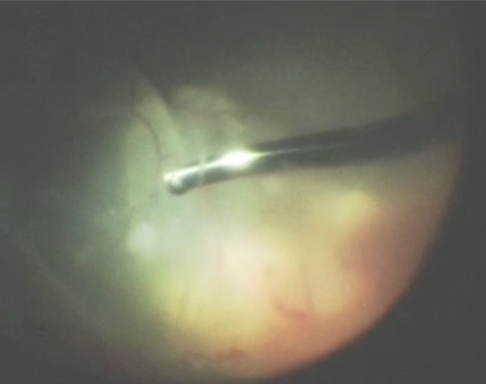

A vitrectomy is an outpatient surgical procedure that is the best way to treat certain ocular conditions. An instrument called a vitrector (see image) is used to cut and suction out the vitreous. Once the vitreous is removed, it never grows back. Instead, fluid in the front part of the eye called aqueous fluid will fill up the space where the vitreous was removed. The eye does not need vitreous to be healthy – sometimes the vitreous is referred to as the appendix of the eye in that it causes nothing but problems for the patient!